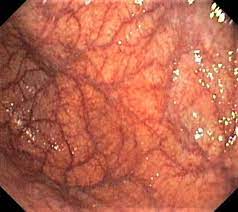

위내시경검사를 통해 진단하며, 검사 중 시행한 조직검사를 통해 심한 정도를 판정한다. 그러나 조직검사를 통한 진단 방법은 시간과 비용 등의 이유로 위축성 위염의 발견이 아닌 위암을 발견하는 것을 목적으로 한다. 따라서 실제 임상에서는 내시경을 이용한 육안 소견을 기반으로 하여 위축성 위염의 유무를 평가한다. 이러한 평가 방법은 환자의 편리성과 비용 효율성을 고려하여 선택된다. 또한, 내시경을 통해 진단할 수 있는 다른 위 질환들도 함께 확인할 수 있다. 따라서 위내시경검사는 다양한 정보를 제공하여 진단의 정확성을 높이는 중요한 도구로 사용된다.